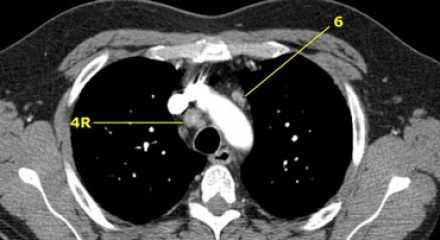

4R. Правые нижние паратрахеальные лимфатические узлы

- Верхняя граница: пересечение нижнего края левой плечеголовной вены с трахеей.

- Нижняя граница: нижний края непарной вены. 4R узлы распространяются до левого края трахеи.

На изображении слева мы видим 4R паратрахеальные узлы. Кроме того здесь представлен узел кнаружи от дуги аорты, то есть 6 группы.